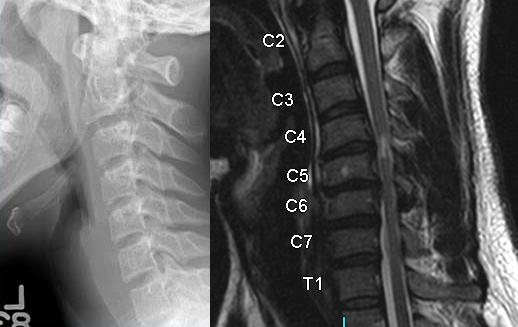

7. A 23-year-old man falls down a flight of stairs while intoxicated and is brought to the emergency room the following morning. On physical exam he has no motor function in his upper and lower extremities. Sensory exam shows diminished but present sensation in the perianal area and in the lower extremities. Reflex exam shows his bulbocavernosus reflex is intact. The inital CT and MRI are seen in Figures A and B. According to the American Spinal Injury Association (ASIA), how would this injury be classified?

FIGURES: A

B

1. ASIA A

DISCUSSION: This patient has some sensory function but no motor function below the injury level. His bulbocavernosus reflex is intact so we know he is no longer in spinal shock. Therefore, he would be classified as an ASIA B.

The imaging studies show a type II odontoid fracture, a congenital fusion at C2/3 and C4/5, and a large soft disc herniation at C3/4 with spinal cord compression and myelomalacia.